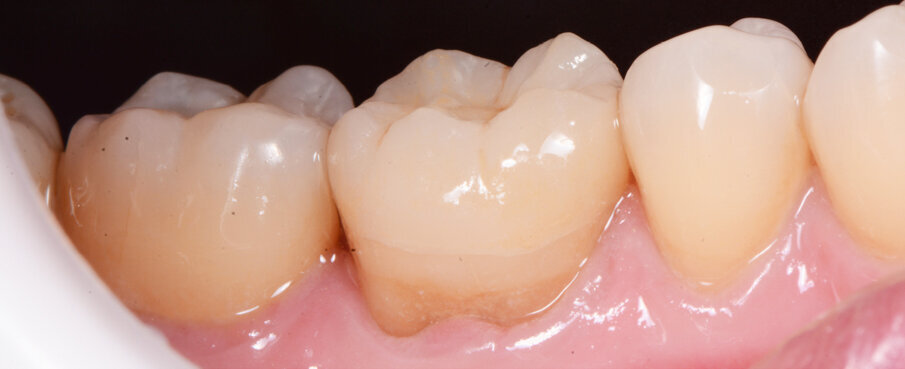

Fig. 12a: Lateral and occlusal view of the completed restoration

Fig. 12b: Lateral and occlusal view of the completed restoration

The adhesive (Tetric N-Bond Universal) was applied and dispersed with a strong stream of air. The dual-curing (DC) version of the Variolink Esthetic luting composite was used for seating due to the thickness of the crown and the low translucency of the ceramic material (Fig. 7). The luting composite was applied into the crown. Then the restoration was seated (Fig. 8) and light cured from each side for two seconds. Excess composite was easy to remove due to the Ivocerin photoinitiator, which provides a fast and thorough cure with a minimum amount of energy (Fig. 9). For final polymerization, the restoration was light-cured from each quarter for 20 seconds (Fig. 10). Figure 11 shows the oral situation after placement of the crown. Although the cement line is located above the gingival margin, it is not visible due to the favourable tone and opacity of the luting composite. Fig. 12 shows an X-ray control image of the restoration: the radiopaque build-up material and cement can be easily told from the tooth structure. This aspect is particularly important in situation where excess cement cannot be seen with the naked eye.